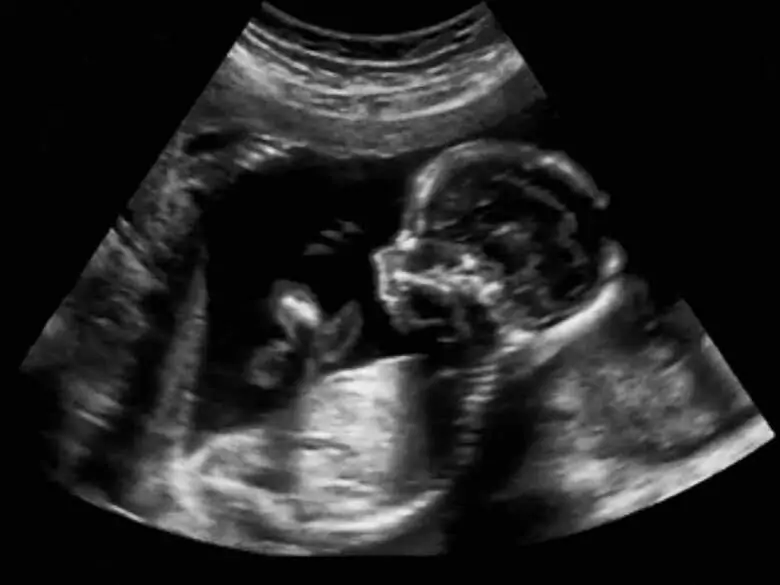

Zespół Jacobsena zaliczany jest do niezwykle rzadkich chorób genetycznych. Choroba pojawia się niezwykle rzadko, dotyka mniej niż jedno dziecko na sto dwadzieścia tysięcy urodzeń. Zespołowi Jacobsena towarzyszy szereg chorób towarzyszących, które wpływają na stan zdrowia dziecka dotkniętego chorobą. Istotna jest więc zarówno wczesna diagnostyka jak i podjęcie odpowiedniego leczenia.